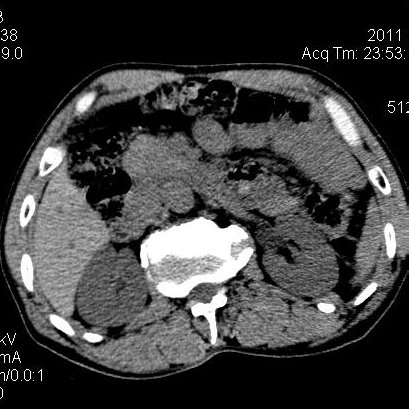

肝左叶发育异常

男性,55岁,骑摩托车摔倒后入院,自述右上腹疼痛

[backcolor=#FF0000]第一次诊断的时候也是这么肯定,可是床旁超声检查并没有发现明显异常,而且患者的一般症状都良好。还好临床只是保守治疗,没有立即手术,第二次复查的时候没有一点变化,又做了MRI检查,没有血肿,

这是一例肝左叶发育异常的,很个性吧~[/backcolor]